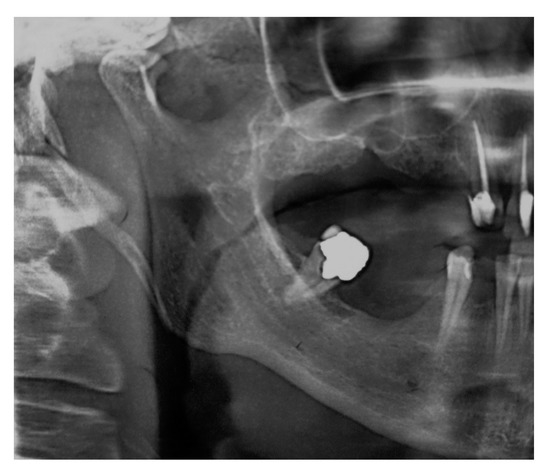

Patient #2′s panoramic X-ray acquisition showed bilaterally pathological nodular elongation of the left and right styloid processes extending beyond the lower border of the mandible (Figure 3); an unerupted impacted maxillary left canine and, on the right side, the sinus mucocele was also observed. A tentative diagnosis was made that the patient had true Eagle’s syndrome due to the unusual panoramic image and pain experiences.

Figure 3. Panoramic X-ray acquisition showing bilaterally pathological nodular elongation of the left and right styloid processes extending beyond the lower border of the mandible; an unerupted impacted maxillary left canine and, on the right side, the sinus mucocele can also be seen.